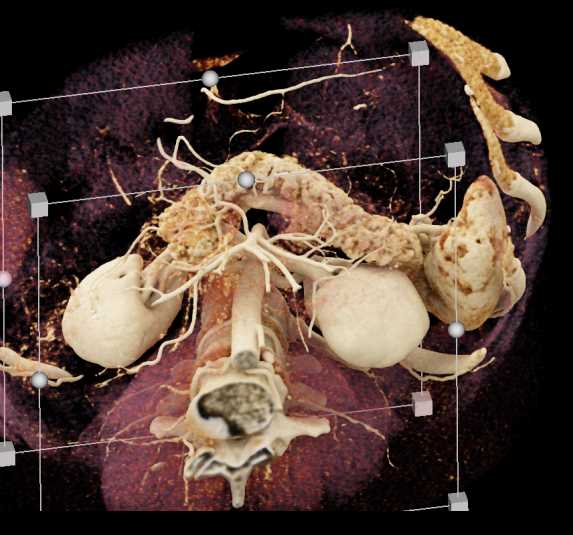

Subtle Neuroendocrine Tumor Body of Pancreas